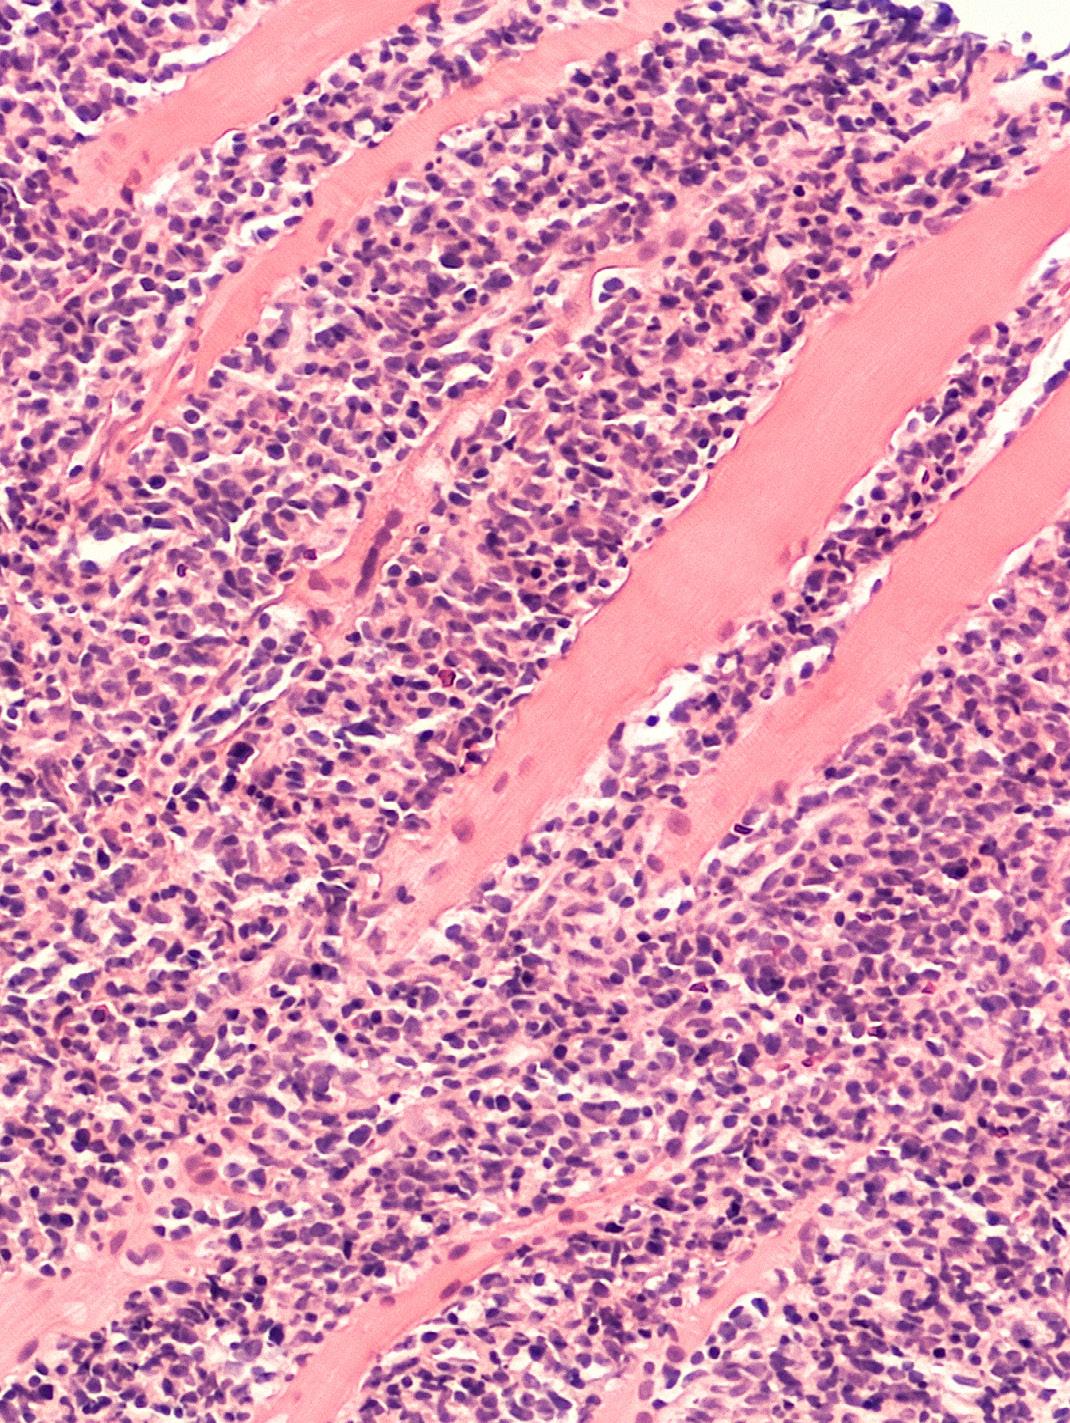

L’augmentation de volume d’un ou de plusieurs ganglions ainsi que les signes cliniques qui peuvent être observés sont des symptômes évocateurs d’un lymphome. Le diagnostic de celui-ci est formellement établi sur base d’une biopsie. Cela consiste à prélever un des ganglions dont le volume a augmenté, ou du tissu de l’organe suspect d’être atteint d’un cancer. Les cellules contenues dans ce ganglion sont ensuite examinées au microscope par un médecin anatomo-pathologiste.

L’examen au microscope (appelé examen histologique ou histologie) permet de poser le diagnostic mais aussi de préciser le type du lymphome. La connaissance précise du type de lymphome est importante pour déterminer le pronostic et le choix du traitement .